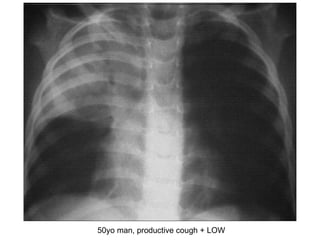

50yo man, productive cough + LOW

CXR- R upper lobe collapse Describe? Opacities/haziness in RUZ + perihilar R horizontal fissure prominent R tracheal deviation Dx? R upper lobe collapse  Causes? Lung Ca/foreign body PTB/pneumonia 2 Ix? Sputum FEME + cytology + AFB Bronchoscopy + biopsy

CXR- R upperlobe collapse Describe? Opacities/haziness in RUZ + perihilar R horizontal fissure prominent R tracheal deviation Dx? R upper lobe collapse Causes? Lung Ca/foreign body PTB/pneumonia 2 Ix? Sputum FEME + cytology + AFB Bronchoscopy + biopsy